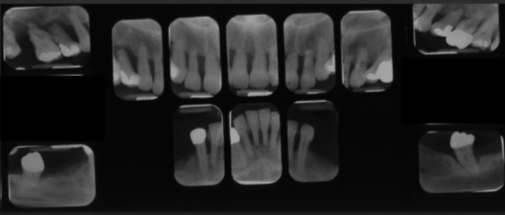

stages

1,2,3,4

grade

a,b,c

moderate to severe horizontal bone loss

advanced stages of perio

extensive horizontal bone loss or extensive vertical defects

osseous defects in furcation of multirooted teeth

floating tooth

bone scar after extraction

periodontal abscess

rapidly destructive lesion originating in deep soft tissue pocket

if acute=no radiographic signs

localized bone loss

less than 30% of sites effected

vertical osseous defects

severe and rapid loss

worse on incisors and first molars

generalized bone loss

more than 30% of sites affected

stage IV perio